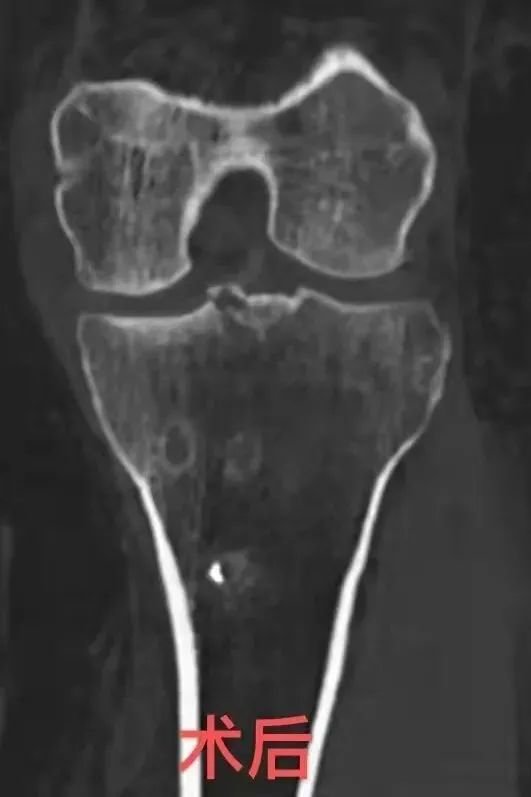

患者被确诊为

滑膜软骨瘤病

“髋关节镜滑膜切除+

游离体取出+

髋关节撞击成型+

盂唇修复”

患者术后恢复很好